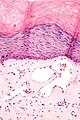

| LM | ectatic superficial dermal vessels with overlying hyperkeratosis (thick stratum corneum); should have "epidermal collarette" (vascular space is surrounded by epidermis on three sides) |

- Ectatic superficial dermal vessels.

- Overlying hyperkeratosis (thick stratum corneum).

- Should have "epidermal collarette".[2]

- Vascular space surrounded by epidermis on three sides.

- Irregular acanthosis.

- Longer rete ridges.